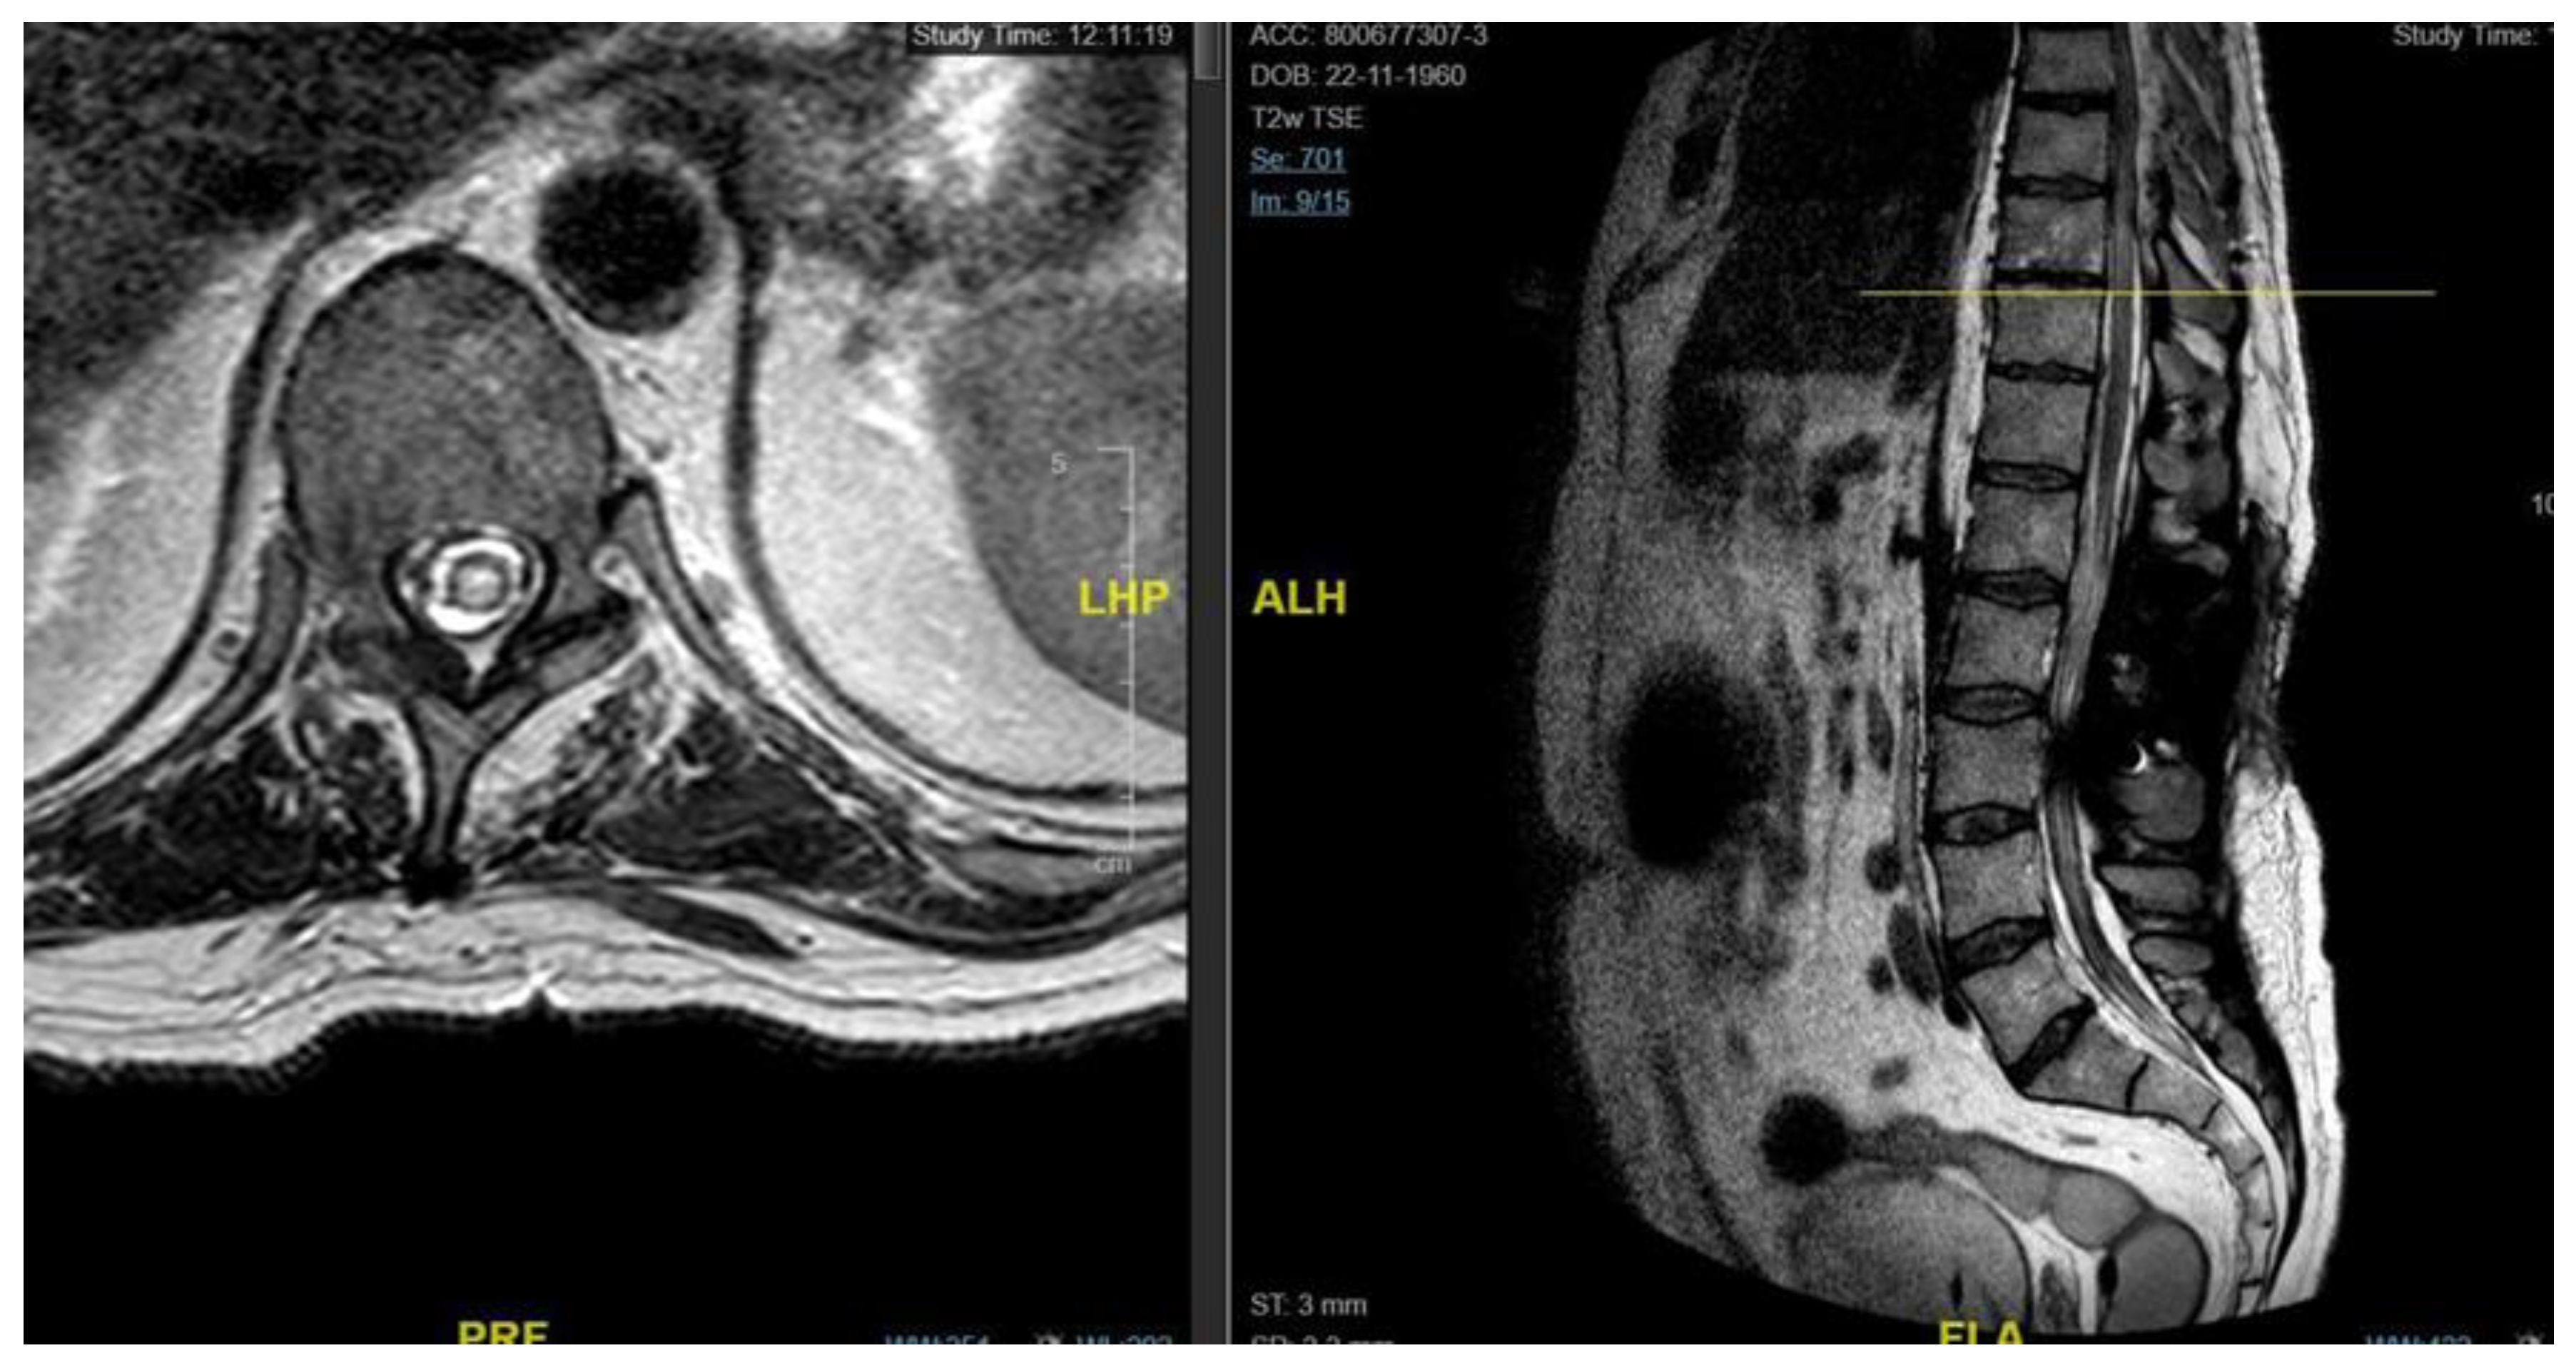

A 62-year-old man, 10 months after surgery for the removal of a spinal cavernoma, developed recurrent left-sided lumbosciatica, paresthesia, hypoesthesia, and an episode of acute urinary retention. Neurological examination revealed weakness in the left lower limb, mild hyperreflexia, and neurogenic bladder. MRI showed an intradural-extramedullary cyst from D3 to D8 and an extradural component from D9 to D11, compressing the spinal cord and causing myelopathy [Figure 4]. The patient underwent a left hemilaminectomy (D6-D10) for cyst removal. Histology confirmed a spinal arachnoid cyst. Postoperatively, the patient remained neurologically stable, the post-operative MRI showed the absence of the anterior cystic collection at the dorsal spine, with only a slight reduction in the area of myelopathy and persistent central spinal cord signal alteration at the D9-10 level [Figure 5]. Eight months later, he experienced worsening of symptoms, including low back pain and paraplegia. The performed MRI revealed a cystic mass from D4 to D8. He underwent a decompressive laminectomy (D5-D10) and cyst fenestration. Postoperative MRI showed resolution of the cyst but an extension of the myelopathic area. Despite these issues, the patient did not experience new neurological deficits over 3 years of follow-up.

Figure 4. Case 3: pre-operative MRI showing an intradural and extradural cyst.

Figure 5. Case 3: post-operative MRI showing the absence of a recurrent cystic formation.